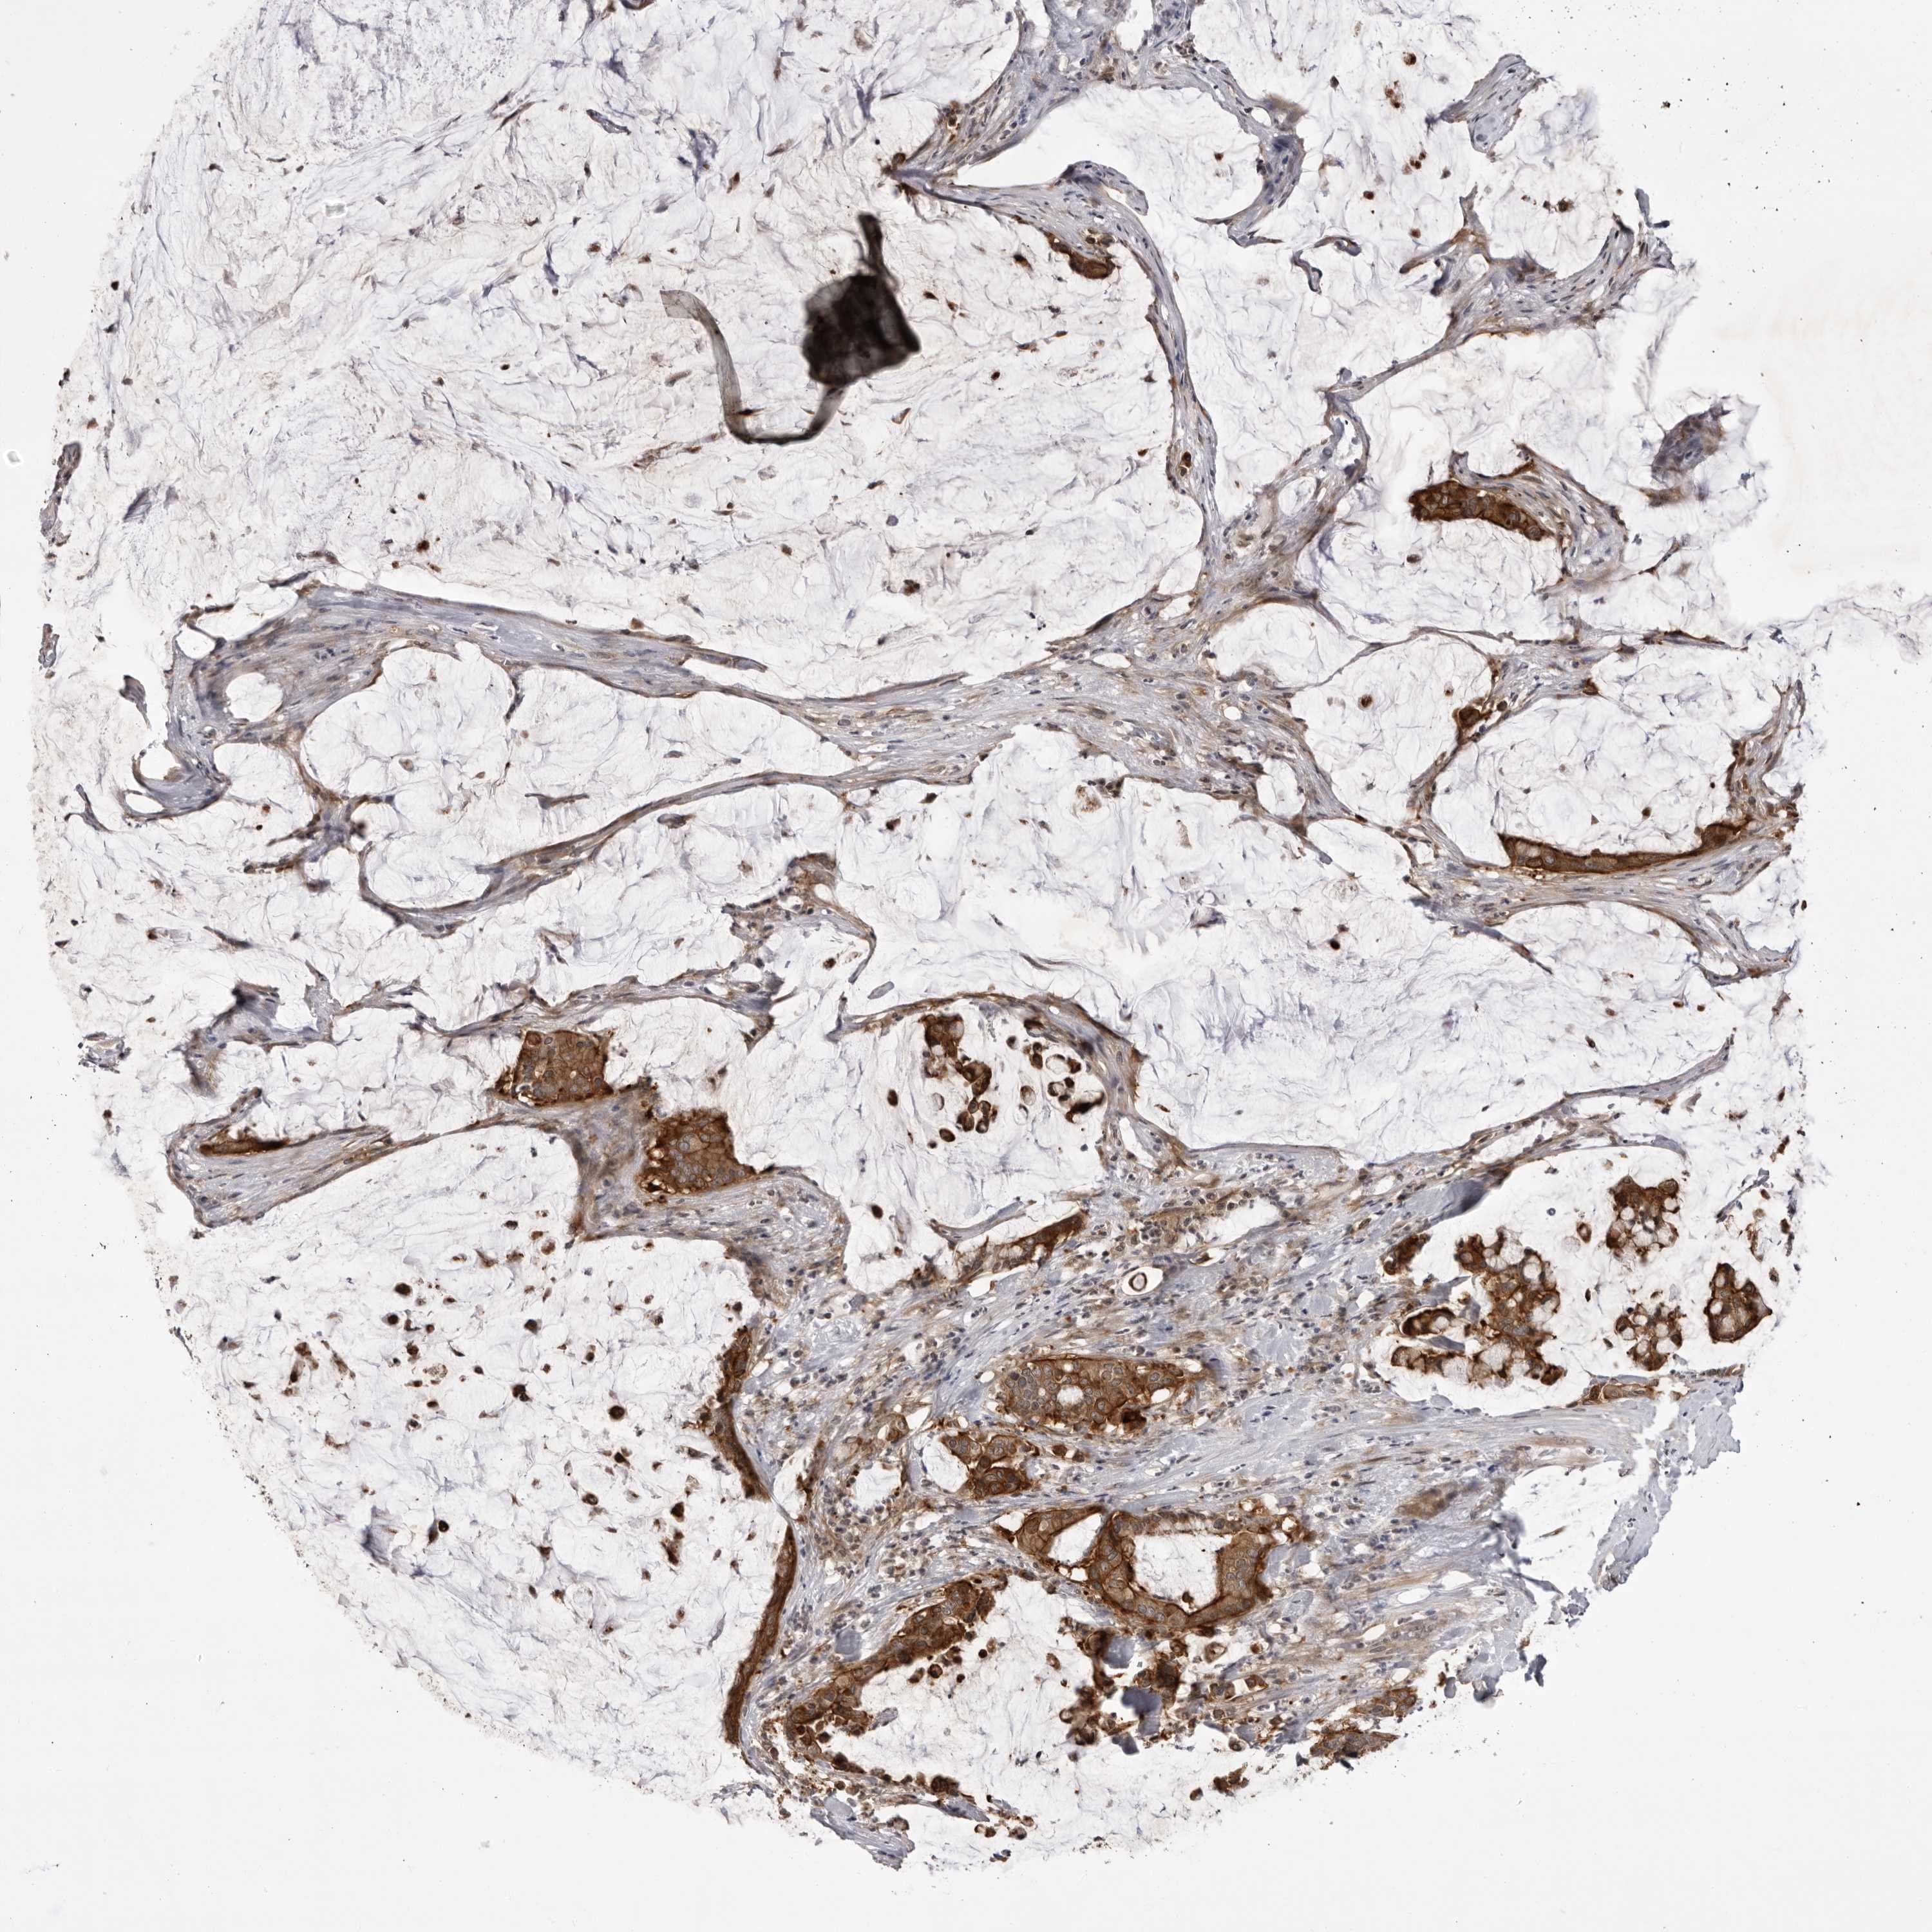

PANCREATIC CANCER - Protein expressioni

A mouse-over function shows sample information and annotation data. Click on an image to view it in a full screen mode. Samples can be filtered based on level of antibody staining by selecting one or several of the following categories: high, medium, low and not detected. The assay and annotation is described here.

Note that samples used for immunohistochemistry by the Human Protein Atlas do not correspond to samples in the TCGA dataset.

Antibody stainingi

Antibody staining in the annotated cell types in the current human tissue is reported as not detected, low, medium, or high, based on conventional immunohistochemistry profiling in selected tissues. This score is based on the combination of the staining intensity and fraction of stained cells.

Each image is clickable and will lead to virtual microscopy that enables deeper exploration of all samples and also displays staining intensity scores, fraction scores and subcellular localization as well as patient and tissue information for each sample.

Antibody HPA023389

Antibody HPA027762

Staining

High

Medium

Low

Not detected

Intensity

Strong

Moderate

Weak

Negative

Quantity

>75%

75%-25%

<25%

None

Location

Nuclear

Cytoplasmic/membranous

Cytoplasmic/membranous,nuclear

Adenocarcinoma, NOS